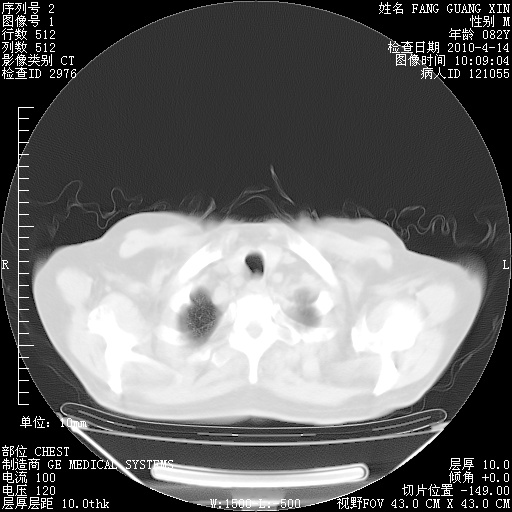

肺部CT平扫未见异常。